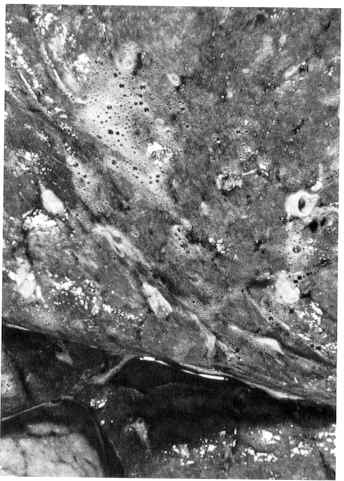

Acute pulmonary edema: severe form of cardiac asthma

Initially, the edema is found in the lower lobes; however, in advanced disease all lobes may be involved.

Sectioning of the lobes reveals a sanguineous fluid consisting of a mixture of air and edema fluid. Loop diuretics such as furosemide, bumetanide, torsemide, and ethacrynic acid are effective in reducing pulmonary edema in CHF.

Figure and description above adapted from "Robbins: The Pathological Basis of Disease" Fifth Edition, p. 96

Pulmonary edema is common in congestive heart failure.

As pulmonary capillary pressures increase, the initial fluid excess is removed by increased lymphatic drainage.

When lymphatic system capacity is exceeded, pulmonary edema occurs.

Radiographic signs include septal lines, bronchial wall thickening and subpleural pulmonary edema.

Figure above and description adapted from "Robbins: The Pathological Basis of Disease" Fifth Edition, p. 96